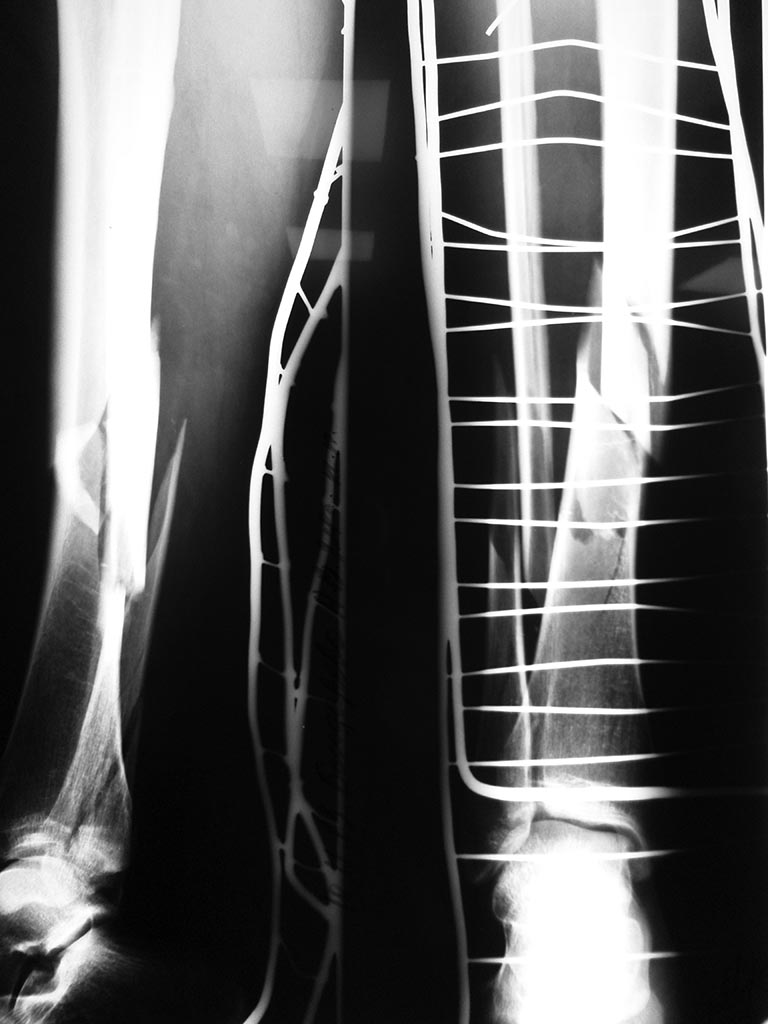

Представляю вашему вниманию случай Ж, 24 лет, не курит, оступилась на скользких ступенях и подвернула ногу,уложена ССВ,кожа спокойная, сосудистых и неврологических расстройств нет, проводится предоперационная подготовка. Ваше мнение каким образом синтезировать малоберцовую кость. прошу обратить внимание, что вовлечена наружная лодыжка.